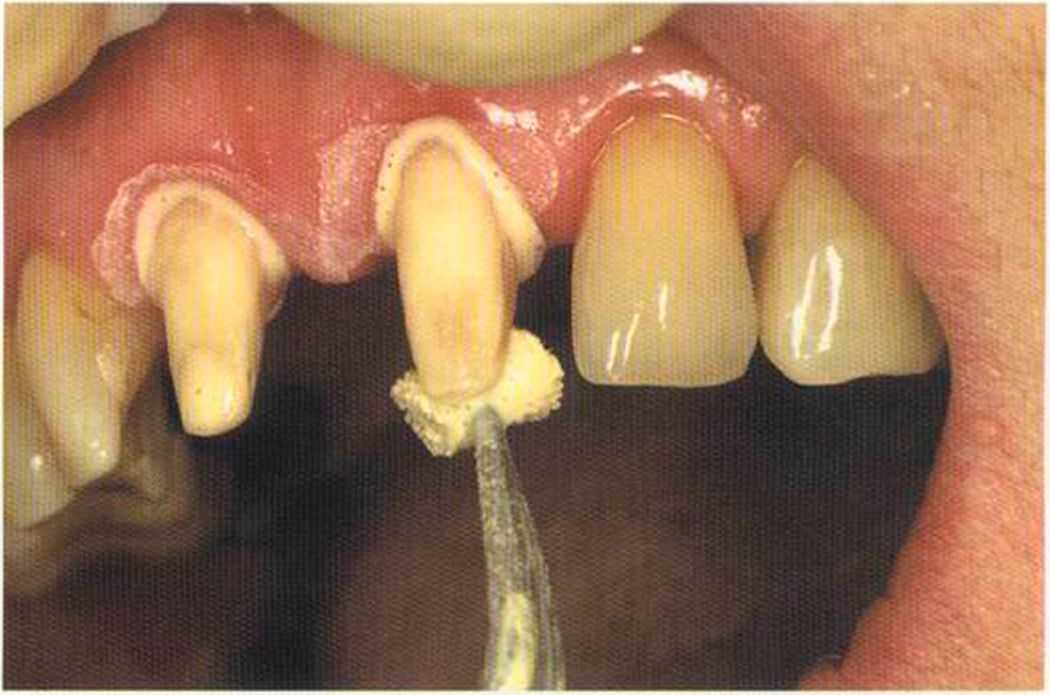

Этот пациент — португалец. Он всю жизнь имел такое положение зубов. Небнорасположенный боковой резец теперь необходимо удалить, а затем воссоздать как эстетику, так и функцию в области фронтальной группы зубов. Планируется изготовить коронки In-Ceram в области 11 и 21 и соединить их вместе из-за увеличивающейся подвижности зубов.

Препарирование, проводимое доктором Риссе, оценивается как очень сложное. Режущие края центральных резцов сильно дивергируют, что создает неудобство при формировании хорошего уступа.

Фото сверху и слева: отличный результат препарирования зубов с уже уложенными нитями для снятия оттиска.